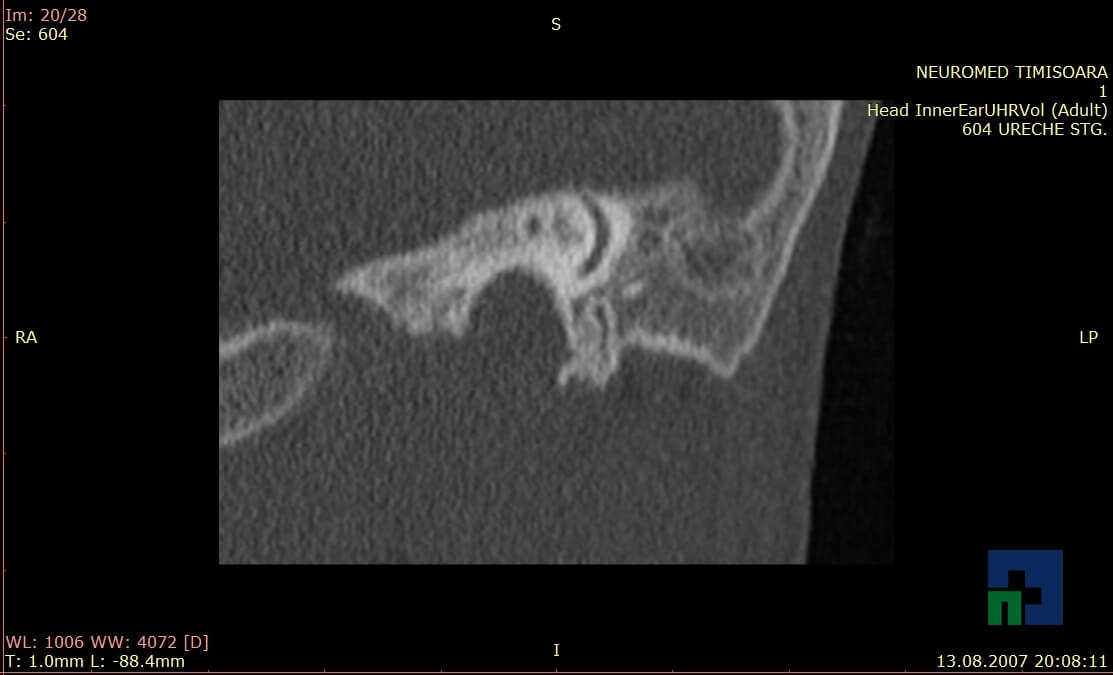

- Diagnosticul traumatismelor de bază de craniu

- Diagnosticul fracturilor:

-

- Unice

- Multiple

- Cu înfundare

- Complexe cranio-sinusale

- Complexe cranio-etmoidale

- Complexe cranio-orbitare

- Complexe cranio-faciale